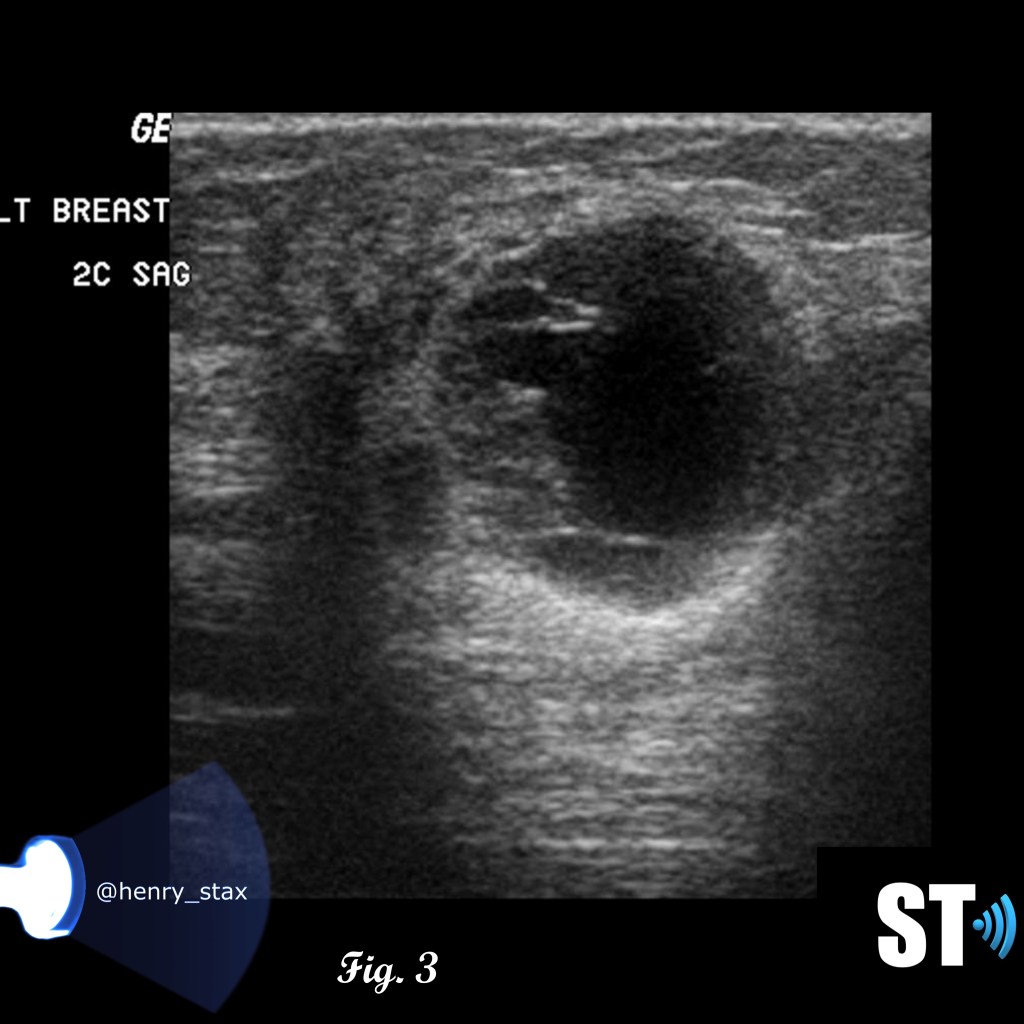

Ultrasound

Patients with suspicious or palpable masses are often referred to ultrasound for further evaluation. Phyllodes tumors can exhibit characteristics similar to fibroadenomas such as; hypoechoic, well demarcated, solid. Features like rapid growth, large size at presentation and cystic areas can raise suspicion for phyllodes.

Fig. 1-3 17 yo Female with complex cystic/solid breast lesion that resulted to be phyllodes.